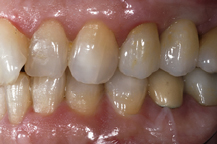

Ceramic Abutment connected to implant

Ceramic crown bonded to abutment

The adjacent images show how a ceramic abutment can enhance a ceramic crown by giving it a more lifelike appearance. Ceramic abutments have to be used with care, however, since their compressive strength is nowhere near that of titanium, gold or other noble metals. Most clinicians feel more comfortable using a metal prosthetic abutment in the posterior molar areas, due to the increased masticatory forces present in these areas.